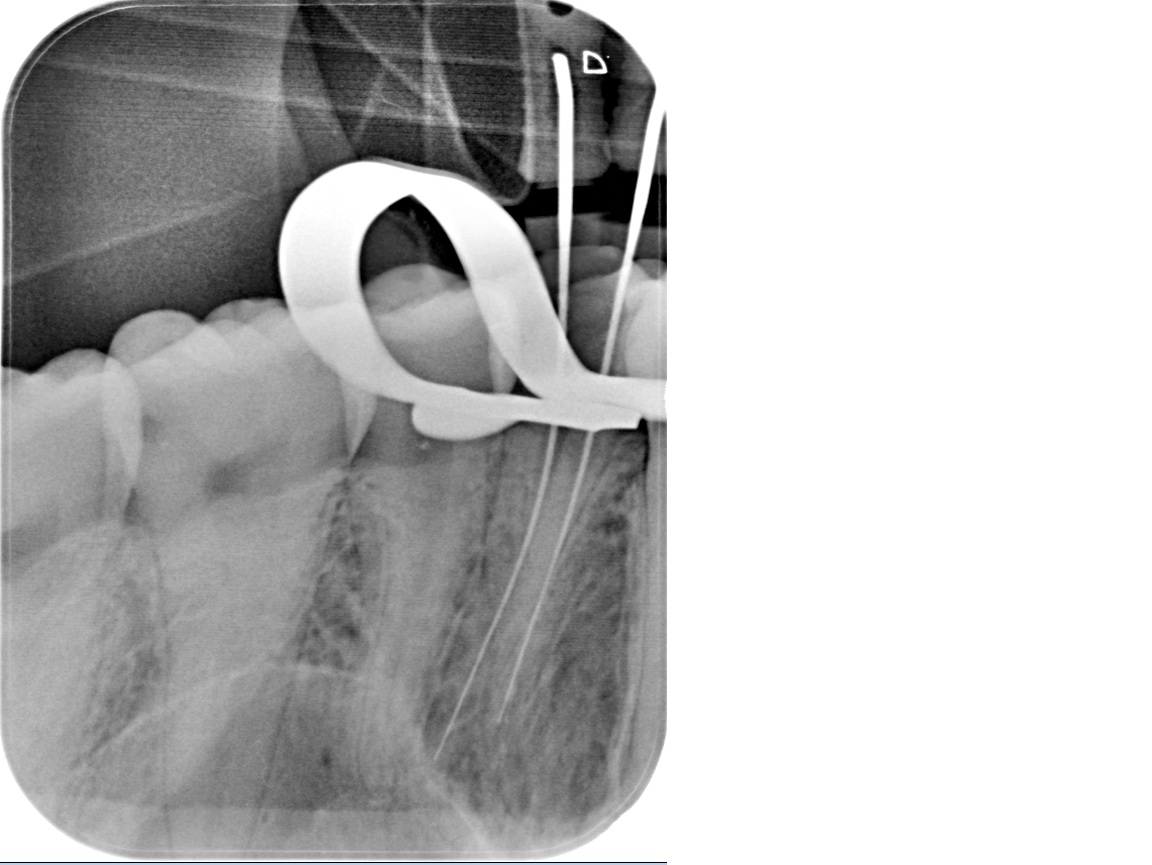

Every procedure is performed under magnification with a rubber dam in place. Electronic length measurement (apex locator) ensures accuracy to the tip of the root. - Thorough cleaning and reliable sealing

- Clinical assessment and plan

We examine the tooth, test its response, and take focused images. When roots are complex or a previous treatment failed, a small 3D scan may be needed for mapping before we discuss and agree on the plan. - Anaesthesia and comfort

Under bright magnified light, a tiny opening is created and every canal located — even the hidden ones that often cause failures elsewhere. - Cleaning and shaping

The canals are shaped with flexible rotary files to create an ideal form for irrigation while preserving tooth strength. - Disinfection

We use activated solutions to eliminate bacteria and flush out microscopic debris, ensuring the system is clean throughout. - Sealing

The canals are filled with a stable, biocompatible material and sealed against future infection. - Immediate protection